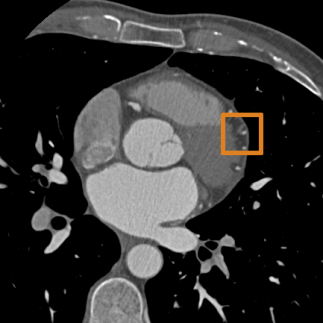

A single CNN is trained to segment six tissues in MR brain images, the pectoral muscle in MR breast images, and the coronary arteries in cardiac CTA. The CNN therefore learns to identify the imaging modality, the visualised anatomical structures, and the tissue classes.

Cardiac CTA –

Ten cardiac CTA scans were acquired on a 256-detector row Philips Brilliance iCT scanner using 120 kVp and 200-300 mAs, with ECG-triggering and contrast enhancement. The reconstructed images had between 0.4 and 0.5 mm in-plane voxel sizes and 0.45/0.90 mm slice spacing/thickness. All images were resampled to isotropic 0.450.450.45 mm3 voxel size. To set a manual reference standard, a human observer traversed the scan in the craniocaudal direction and painted voxels in the main coronary arteries and their branches in the axial plane.

Fig. 2 shows the results of the described quantitative analysis, performed at intervals of 1000 mini-batches per task. As the networks learned, the obtained Dice coefficients increased and the stability of the results improved. For each segmentation task, the learning curves were similar for all experiments. Nevertheless, slight differences were visible between the obtained learning curves. To assess whether these differences were systematic or caused by the stochastic nature of CNN training, the training experiment using only brain MR data (Experiment 1) was repeated (dashed line in Fig. 2), showing similar inter-experiment variation. Fig. 3 shows a visual comparison of results obtained for the three different tasks. For all three tasks, all four networks were able to accurately segment the target tissues.